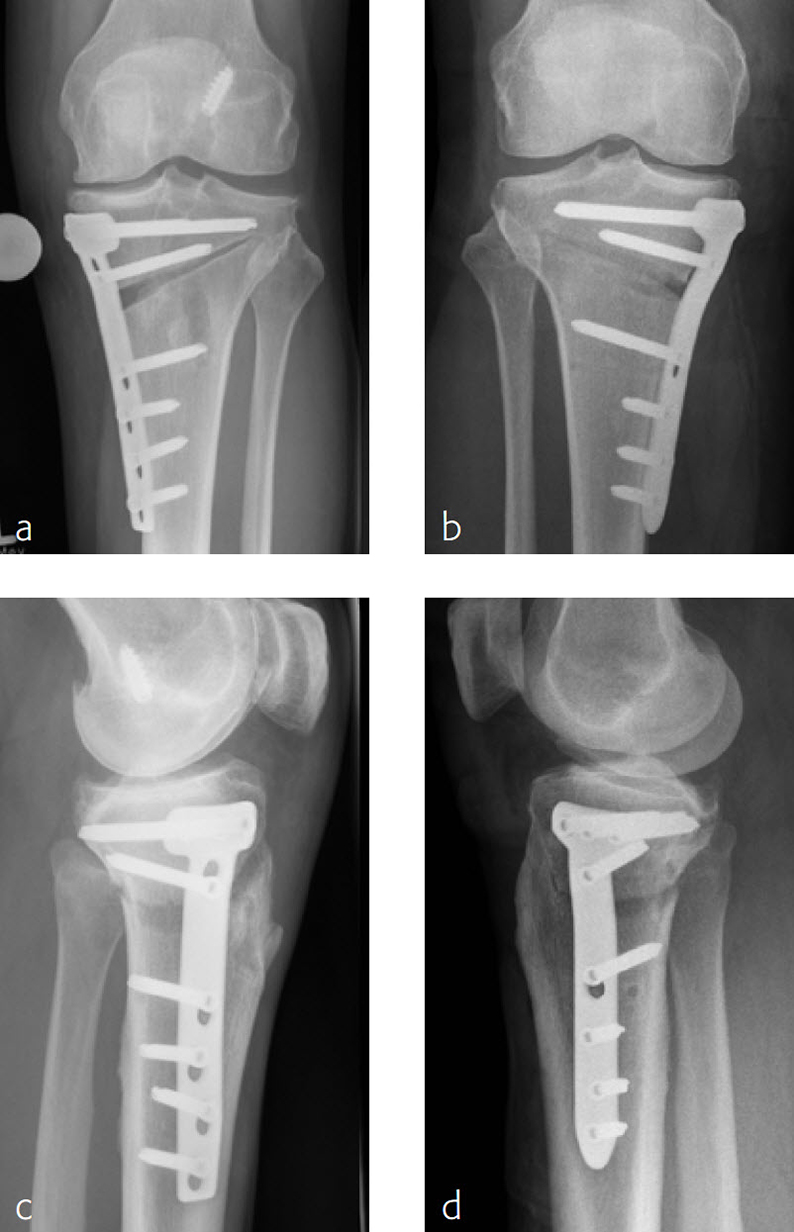

The TomoFix Anatomical Medial High Tibial Plate is contoured to provide an anatomical fit. When compared with the TomoFix Standard and small plates, the new design is intended to reduce both implant prominence

and postoperative implant irritation. Fig 1 shows x-rays from one patient.